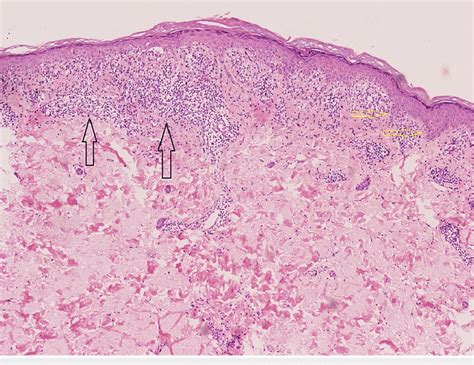

Histopathological analysis of lichenoid keratosis reveals a pronounced lichenoid inflammatory infiltrate that is nearly identical to that seen in lichen planus. This infiltrate is typically band-like and obscures the dermal-epidermal junction.

The epidermis often shows apoptotic keratinocytes (vacuolar alteration of the basal cell layer) and may exhibit epidermal acanthosis, hypergranulosis, and hyperkeratosis. Some histological features that may be present to differentiate lichenoid keratosis from lichen planus include parakeratosis and an inflammatory infiltrate containing scattered eosinophils and plasma cells. Solar elastosis and acanthosis are also frequently observed, particularly in sun-exposed skin.

In a study of 14 patients, histopathological findings indicated that all cases exhibited a lichenoid inflammatory infiltrate obscuring the dermal-epidermal junction and vacuolar alteration of the basal cell layer. The lesions frequently showed focal parakeratosis (79%), melanophages (79%), hyperkeratosis (71%), and necrotic keratinocytes (71%). Solar elastosis (50%) and acanthosis (43%) were also common. Notably, some sections showed skin with lichenoid inflammation and mild overlying hyperkeratosis with very rare parakeratosis, no significant basal atypia, and rare eosinophils. The lymphocytes did not exhibit apparent atypia.

Histology can resemble lichen planus or a lichenoid drug eruption, with some slight differences. The lesions may show focal parakeratosis, melanophages, and necrotic keratinocytes.